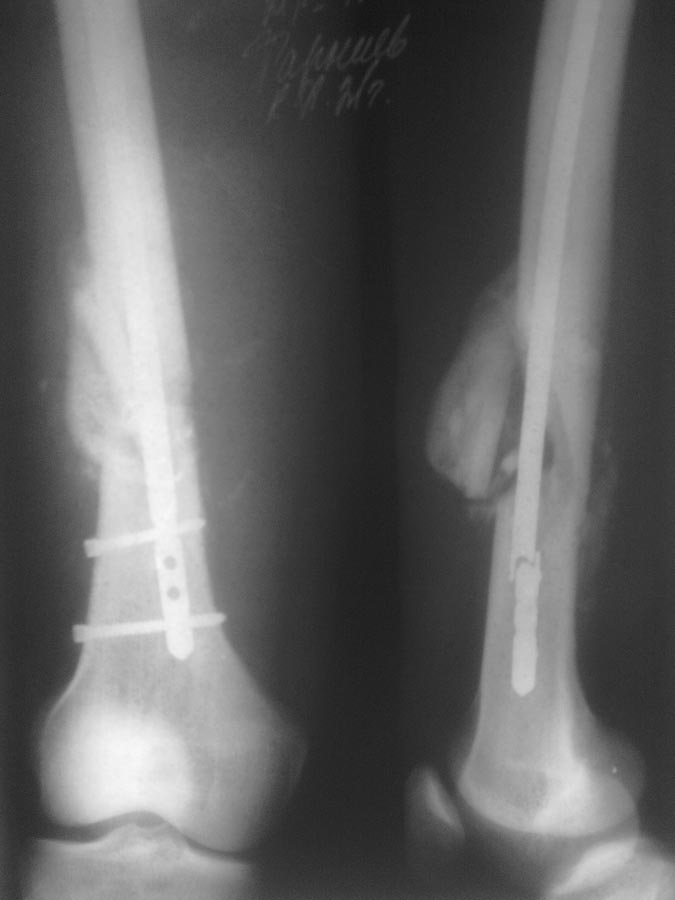

Пациенту ровно полтора месяца назад проводилось оперативное лечение оскольчатого перелома н/3 бедренной кости БИОС.

Гвоздь № 9. Антеградно. Место перелома не открывалось. Возраст пациента 21г. Со слов нагрузку давал не более 30 проц. от веса тела с четвертой недели. На 45 день гвоздь ломается, неосторожно перевернулся в кровати. Вопрос: что делать? Заранее спасибо!

Имя     : лЯБН0237.jpg